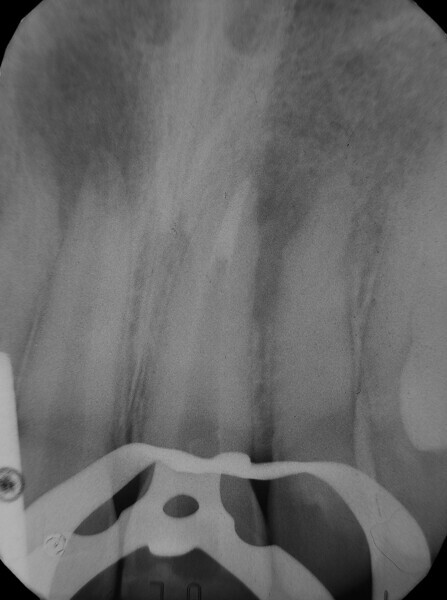

Irrigating the root canal: A case report